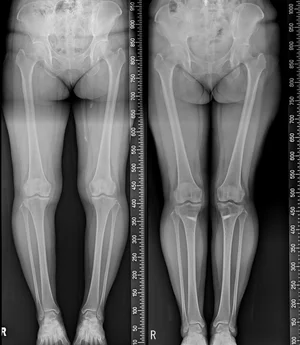

휜다리는 무릎의 건강상태와 걸음걸이, 생활습관, 연령에 따라 ▲내반슬 ▲외반슬 ▲반장슬 등으로 구분되며, 좌식생활이 익숙한 한국인에게는 서 있을 때 양 무릎이 닿지 않고 벌어져 있어 다리가 밖으로 휘어져 있는 내반슬이 주로 해당된다.